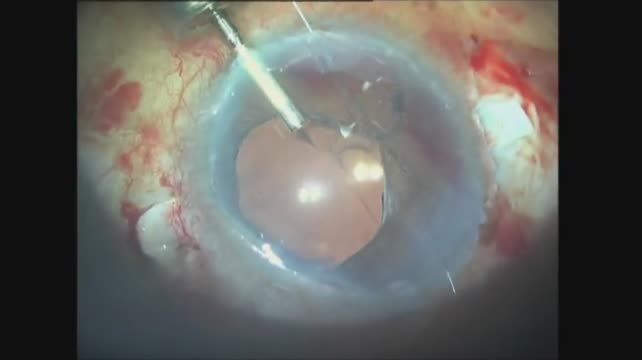

Traumatic Aniridia

Drs. A. Abolhassani, K. Sheibani, and R. Pourmatin